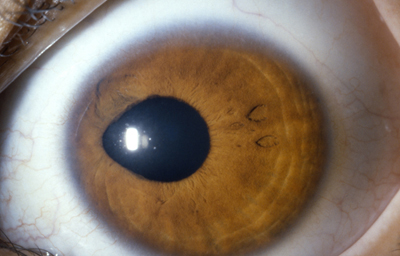

Anomalias del Estroma: Hiperplasia, Hipoplasia

Hiperplasia

Archivo fotográfico Dr. Francisco Barraquer.